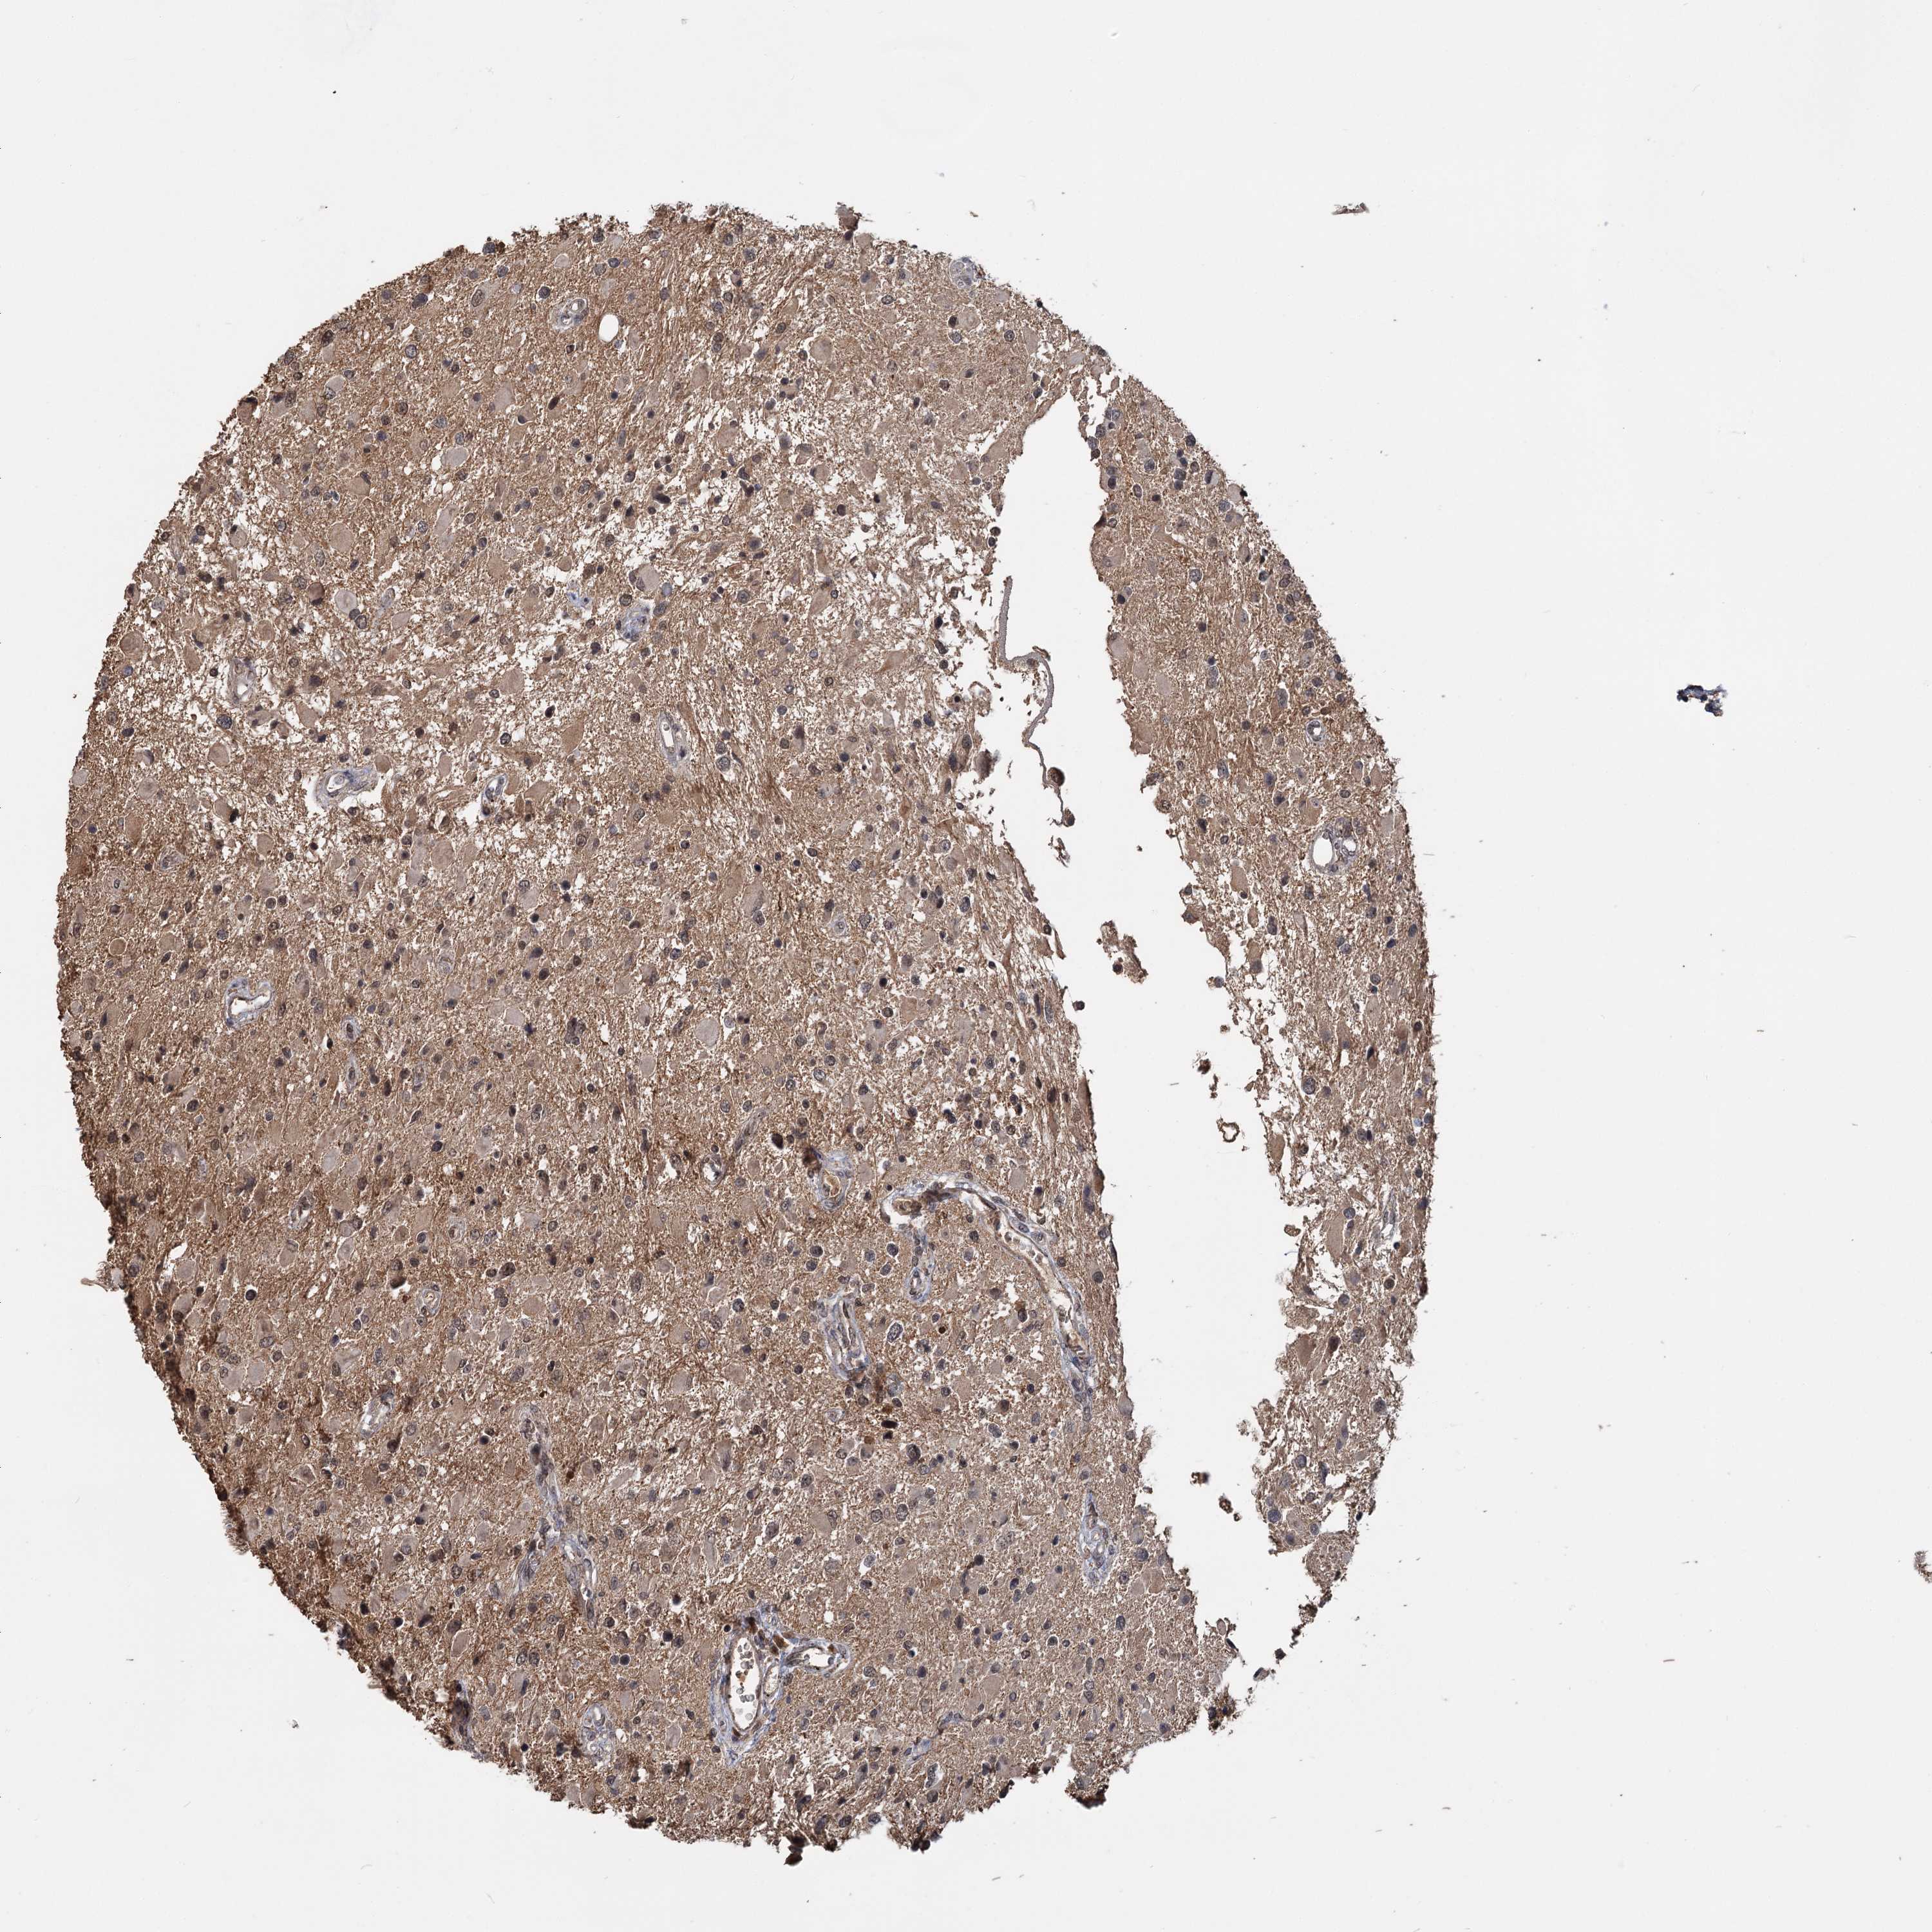

GLIOMA - Protein expressioni

A mouse-over function shows sample information and annotation data. Click on an image to view it in a full screen mode. Samples can be filtered based on level of antibody staining by selecting one or several of the following categories: high, medium, low and not detected. The assay and annotation is described here.

Note that samples used for immunohistochemistry by the Human Protein Atlas do not correspond to samples in the TCGA dataset.

Antibody stainingi

Antibody staining in the annotated cell types in the current human tissue is reported as not detected, low, medium, or high, based on conventional immunohistochemistry profiling in selected tissues. This score is based on the combination of the staining intensity and fraction of stained cells.

Each image is clickable and will lead to virtual microscopy that enables deeper exploration of all samples and also displays staining intensity scores, fraction scores and subcellular localization as well as patient and tissue information for each sample.

Antibody HPA038497

Antibody HPA038498

Staining

High

Medium

Low

Not detected

Intensity

Strong

Moderate

Weak

Negative

Quantity

>75%

75%-25%

<25%

None

Location

Nuclear

Cytoplasmic/membranous

Cytoplasmic/membranous,nuclear

Glioma, malignant, High grade

Glioma, malignant, Low grade